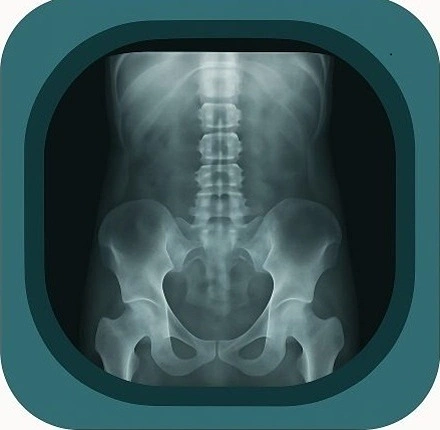

Explore high-quality X-ray anatomy from head to toe. Our database features carefully labelled images to visualize fine structures—perfect for radiologists, students, and surgeons.